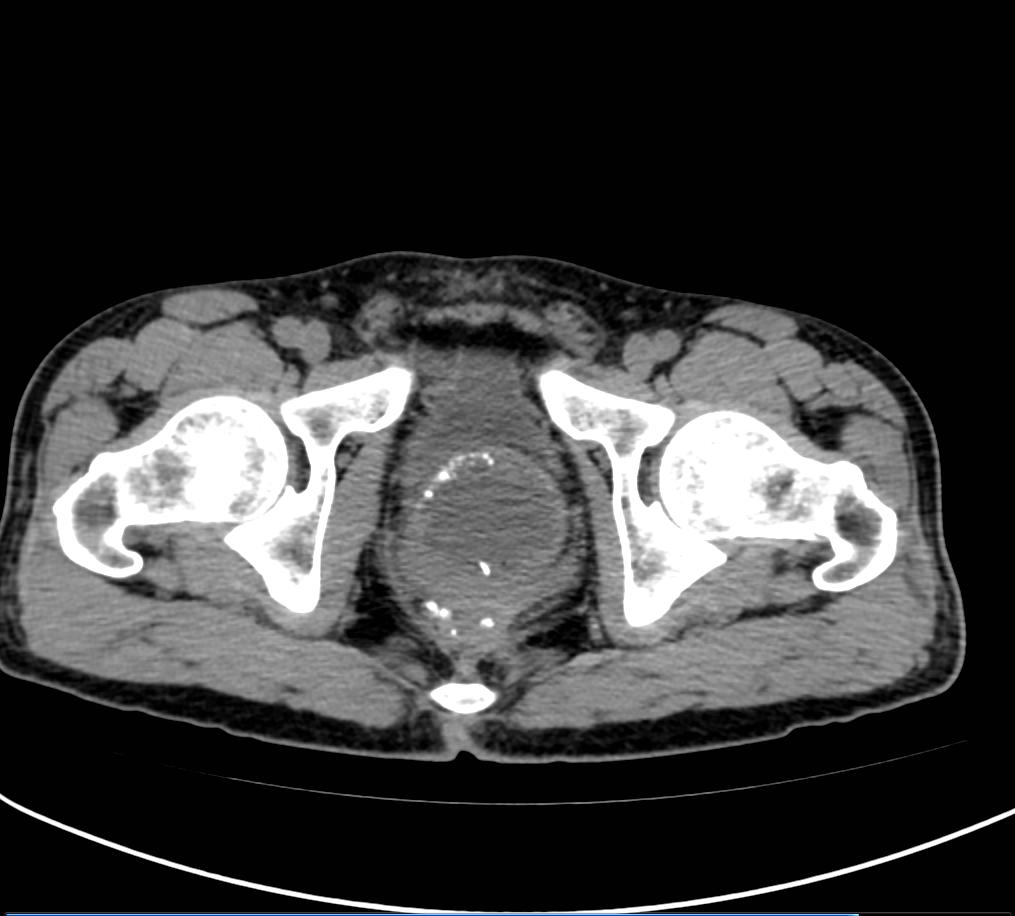

术前MRI影像

刘先生入院后完善了一系列术前检查。考虑到情况比较复杂,傅教授亲自为他进行了肠镜检查评估。肠镜下见齿线上3cm吻合口瘢痕样改变,明显狭窄,肠镜可勉强通过,肠管坚硬,没有收缩能力。